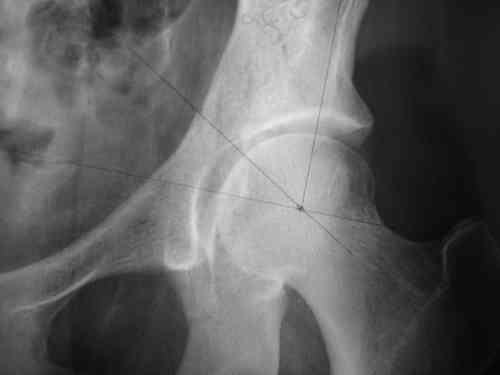

Dear group, 30 years age female MVA front seat, head trauma + post column left acetabular fracture, 2.5 weeks skeletal traction. She is now conscious but still confused without any surgical treatment for brain edema.

Latest X rays and CAT is attached. Fracture within first 1.5 cm from the weight bearing dome, although AP and Obtrator oblique good, iliac oblique view reveals some displacement. I'm not sure that nonsurgical treatment will be OK Hüseyin Demirors Baskent University Dept of Orthopedics and Travmatology Ankara TURKEY